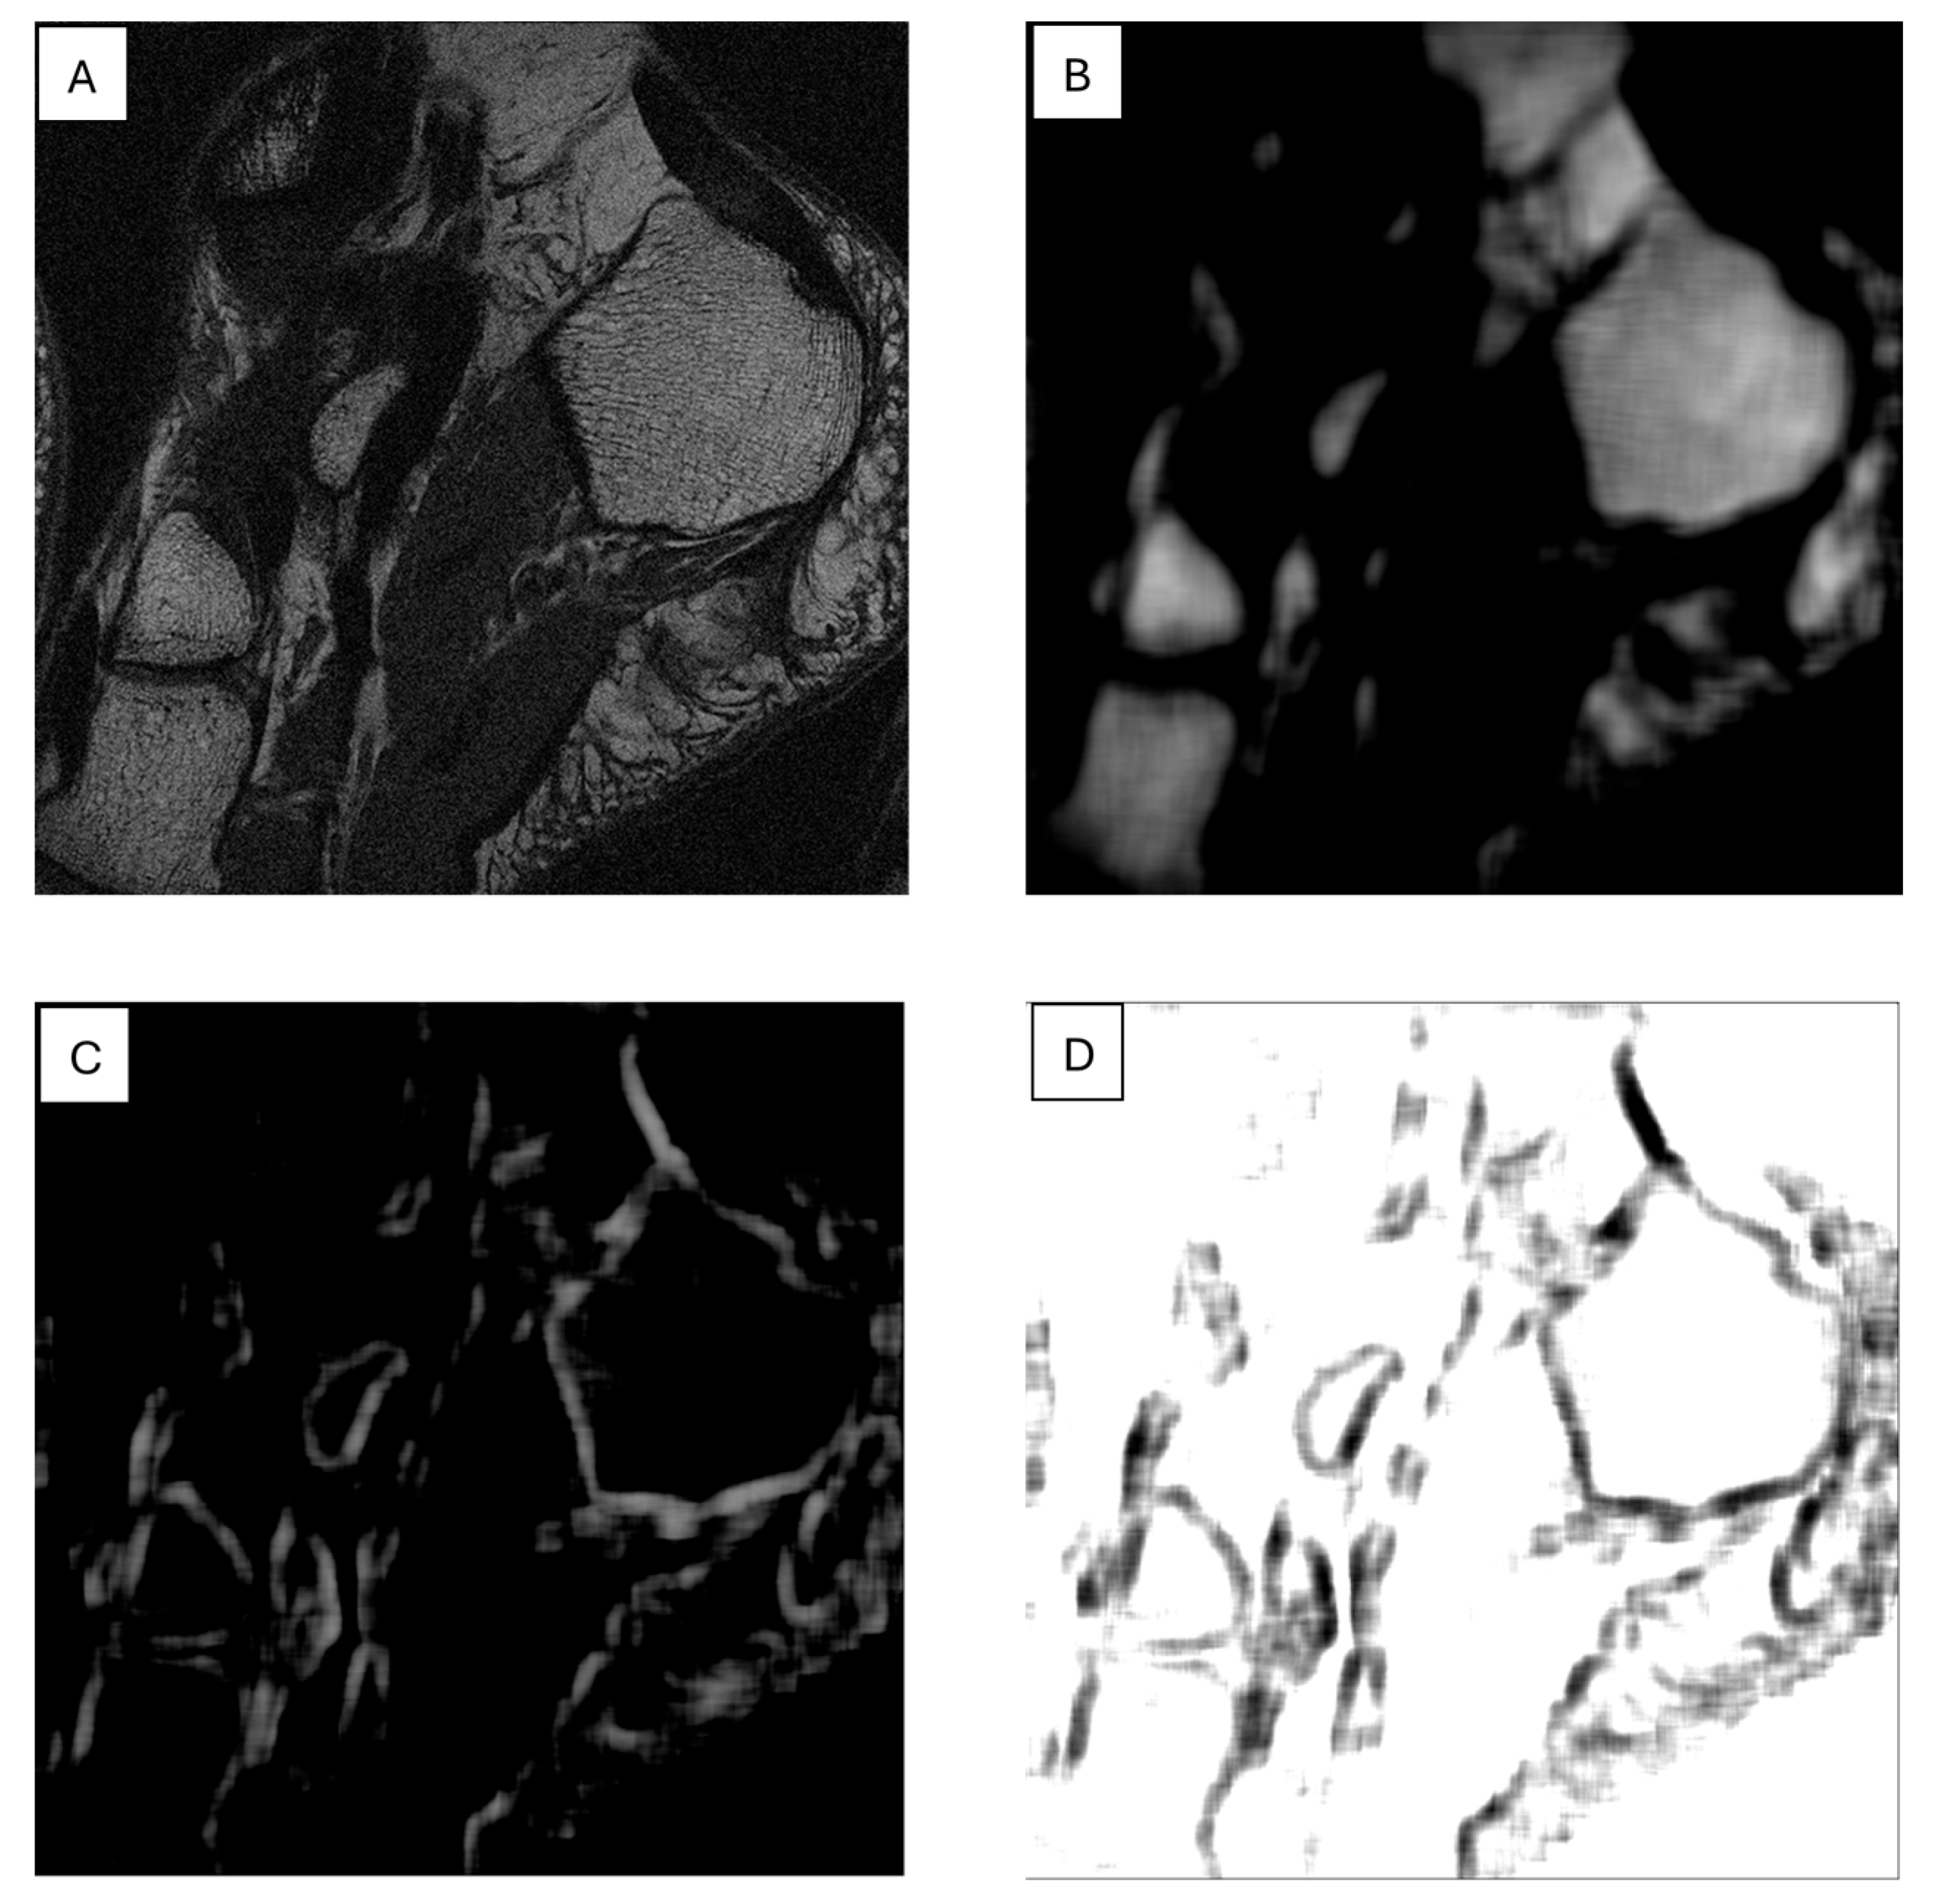

Another example of using such maps for image segmentation is shown in Figure 5, determined for the SumAverage parameter from GLCM for a 15 × 15-pixel sliding window across the T1W MR image of a foot cross-section; bone regions are shown on this map as smooth areas with a small range of brightness levels, which allows them to be relatively easily distinguished from other regions. Texture feature maps can also be used for edge detection. Figure 5C,D shows such maps, obtained for the SumOfSquares (GLM) and Sigma (autoregressive model) features, respectively, in which the edges shown define bone tissue regions. An example of a texture map application combined with an active contour model for biomedical image segmentation is discussed in reference [105].

Figure 5.

T1W MR image of the foot bone (A); feature maps calculated for this image: SumAverage (B); SumOfSquares (C); and Sigma (D).